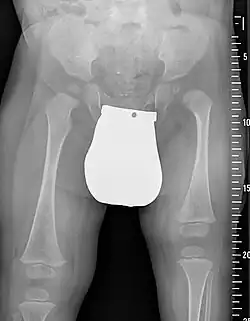

Der Proximale Femurdefekt (englisch Proximal femoral focal deficiency, PFFD) ist eine seltene angeborene Fehlbildung des oberen Endes des Oberschenkelknochens (Femur). Sie tritt meistens einseitig auf. Die Ausprägung reicht von einer leichten Verkürzung bis zum völligen Fehlen des Femurs.

Leitsymptom ist die Beinverkürzung. Ausgeprägte Formen fallen gleich nach der Geburt auf; mildere Formen werden erst im Kleinkindalter erkannt. Da im Röntgenbild nur die knöchernen Anlagen erkennbar sind, kann in den ersten Lebensjahren die Sonografie sinnvoll sein. Die Muskulatur ist regelrecht angelegt, kann aber hypoplastisch sein.[5]